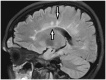

Black Hole

Black holes are areas that, with respect to normal appearing white matter, appear hypointense in T1-weighted images (T1WI) (Fig. 1), and hyperintense in T2-weighted images (T2WI), and are commonly seen in multiple sclerosis (MS) (1). Histopathologically, chronic black holes are related to severe tissue damage, caused by axon loss and demyelination (1,2). Acute black holes represent a group of lesions caused by edema, demyelination and axonal injury (2).

caption a8Black hole sign.